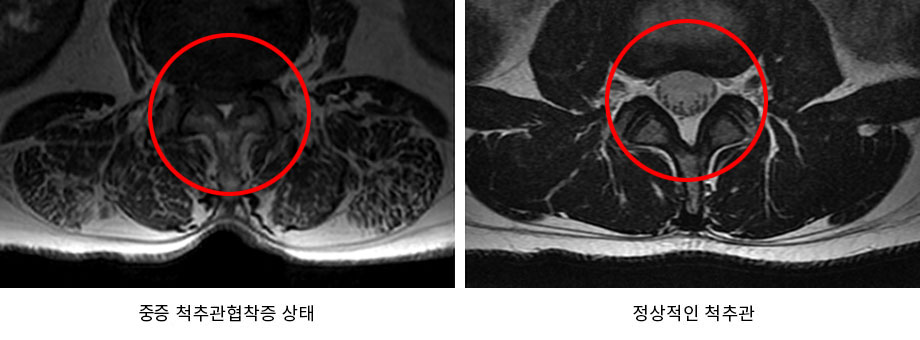

척추관협착증

■ 허리가 굽는 척추협착증이란?

나이가 들면 우리의 몸도 같이 나이가 들게 됩니다. 우리 몸을 지탱해주는 척추 또한 나이를 먹으면서 퇴행되어 기능이 떨어지고, 약해지게 됩니다. 이러한 퇴행으로 인해 발생하는 대표적인 척추질환이 척추협착증입니다. 척추협착증은 척추를 둘러싸고 있는 근육과 인대가 퇴행되어 제 기능을 하지 못하게 되면서 척추관 내 황색인대가 비정상적으로 부풀어 오르게 됩니다. 척추관 내 황색인대가 부풀어 오름에 따라 척추관의 공간이 줄어들게 되면서 신경을 압박하게 되는데, 그로 인해 통증이 발생하는 질환입니다.